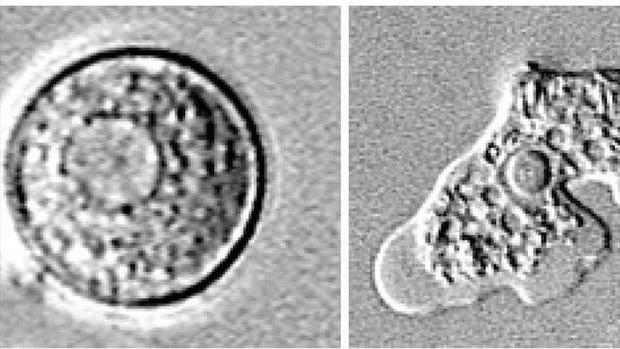

네글레리아 파울러리 아메바는 수심이 얕고 수온이 높은 호수나 강가에 살며, 물과 함께 코로 들어온 뒤 기관을 통해 뇌로 침입해 뇌세포를 파괴하는 것으로 알려져 있다. 전염성은 없지만 아메바에 감염된 지 1~12일 사이에 급작스럽게 사망하기 때문에 예방과 치료가 어려운 편이다. 감염되면 극심한 두통과 고열, 환각증상을 보인다.